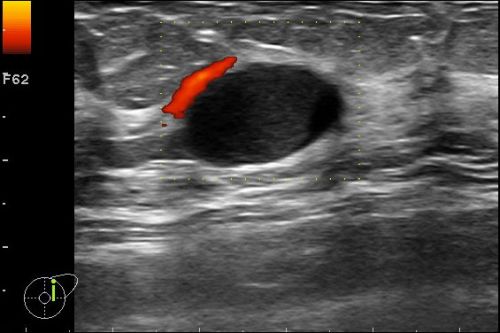

Axilläre Sonographie & Wächterlymphknoten, besondere Befunde, DD Narbe/Rezidiv etc., 3D-Sonographie, Elastographie, Ductussonographie, leitlinienorientiertes Management des Mamma-Ca, anwendungsbezogene Ultraschallthemen, ausreichend Zeit für Diskussionen, praktische Übungen, Fallbeispiele aus der Praxis, Kasuistiken u.a.